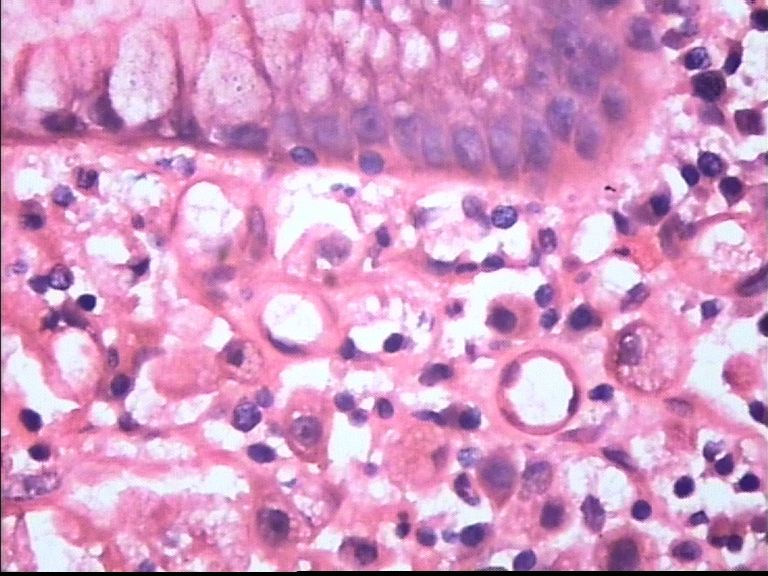

胃部溃疡3cm 53岁 男

• 胃部溃疡3cm 53岁 男图4

图4

仅此局部形态,应该是印戒细胞癌,最好有更多的背景资料

印戒细胞癌

倾向印戒细胞癌

诊断印戒细胞癌

印戒细胞癌高度可疑,建议做:CK、CD68、PAS帮助诊断。